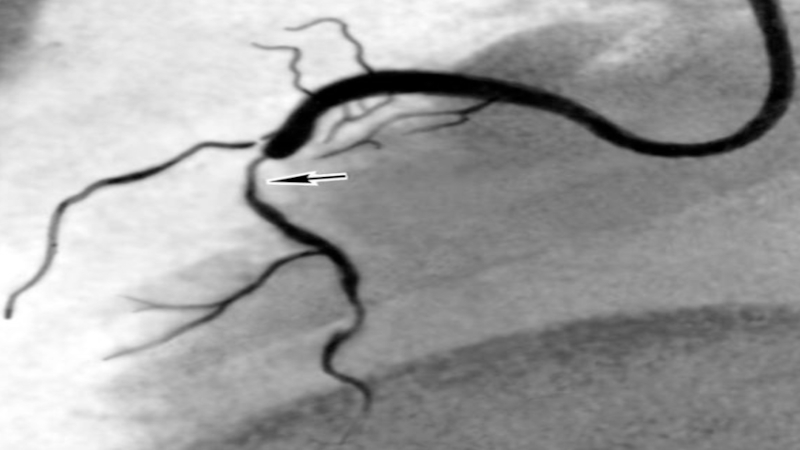

Слайд 27Ангиография

локализация стеноза (окклюзии)

сегментарный уровень стеноза

степень стеноза (% стеноза по диаметру,

% по площади, гемодинамическая значимость: до 50% - гемодинамически незначимые

50-70% - пограничные стенозы, 70% - и выше – критические стенозы,100% - окклюзия)

длина пораженного участка (короткий, длинный, диффузный)

конфигурация и анатомия поражения

количество пораженных артерий

морфология стеноза

коллатеральное кровообращение

степень перфузии в сосуде

Слайд 28Ангиография

Хирург при проведении ангиографии должен прекрасно ориентироваться в рентген анатомии

сосудов исследуемого органа, т.к. для получения наиболее достоверной информации о

поражении сосудов необходимо производить ангиографию в различных проекциях.